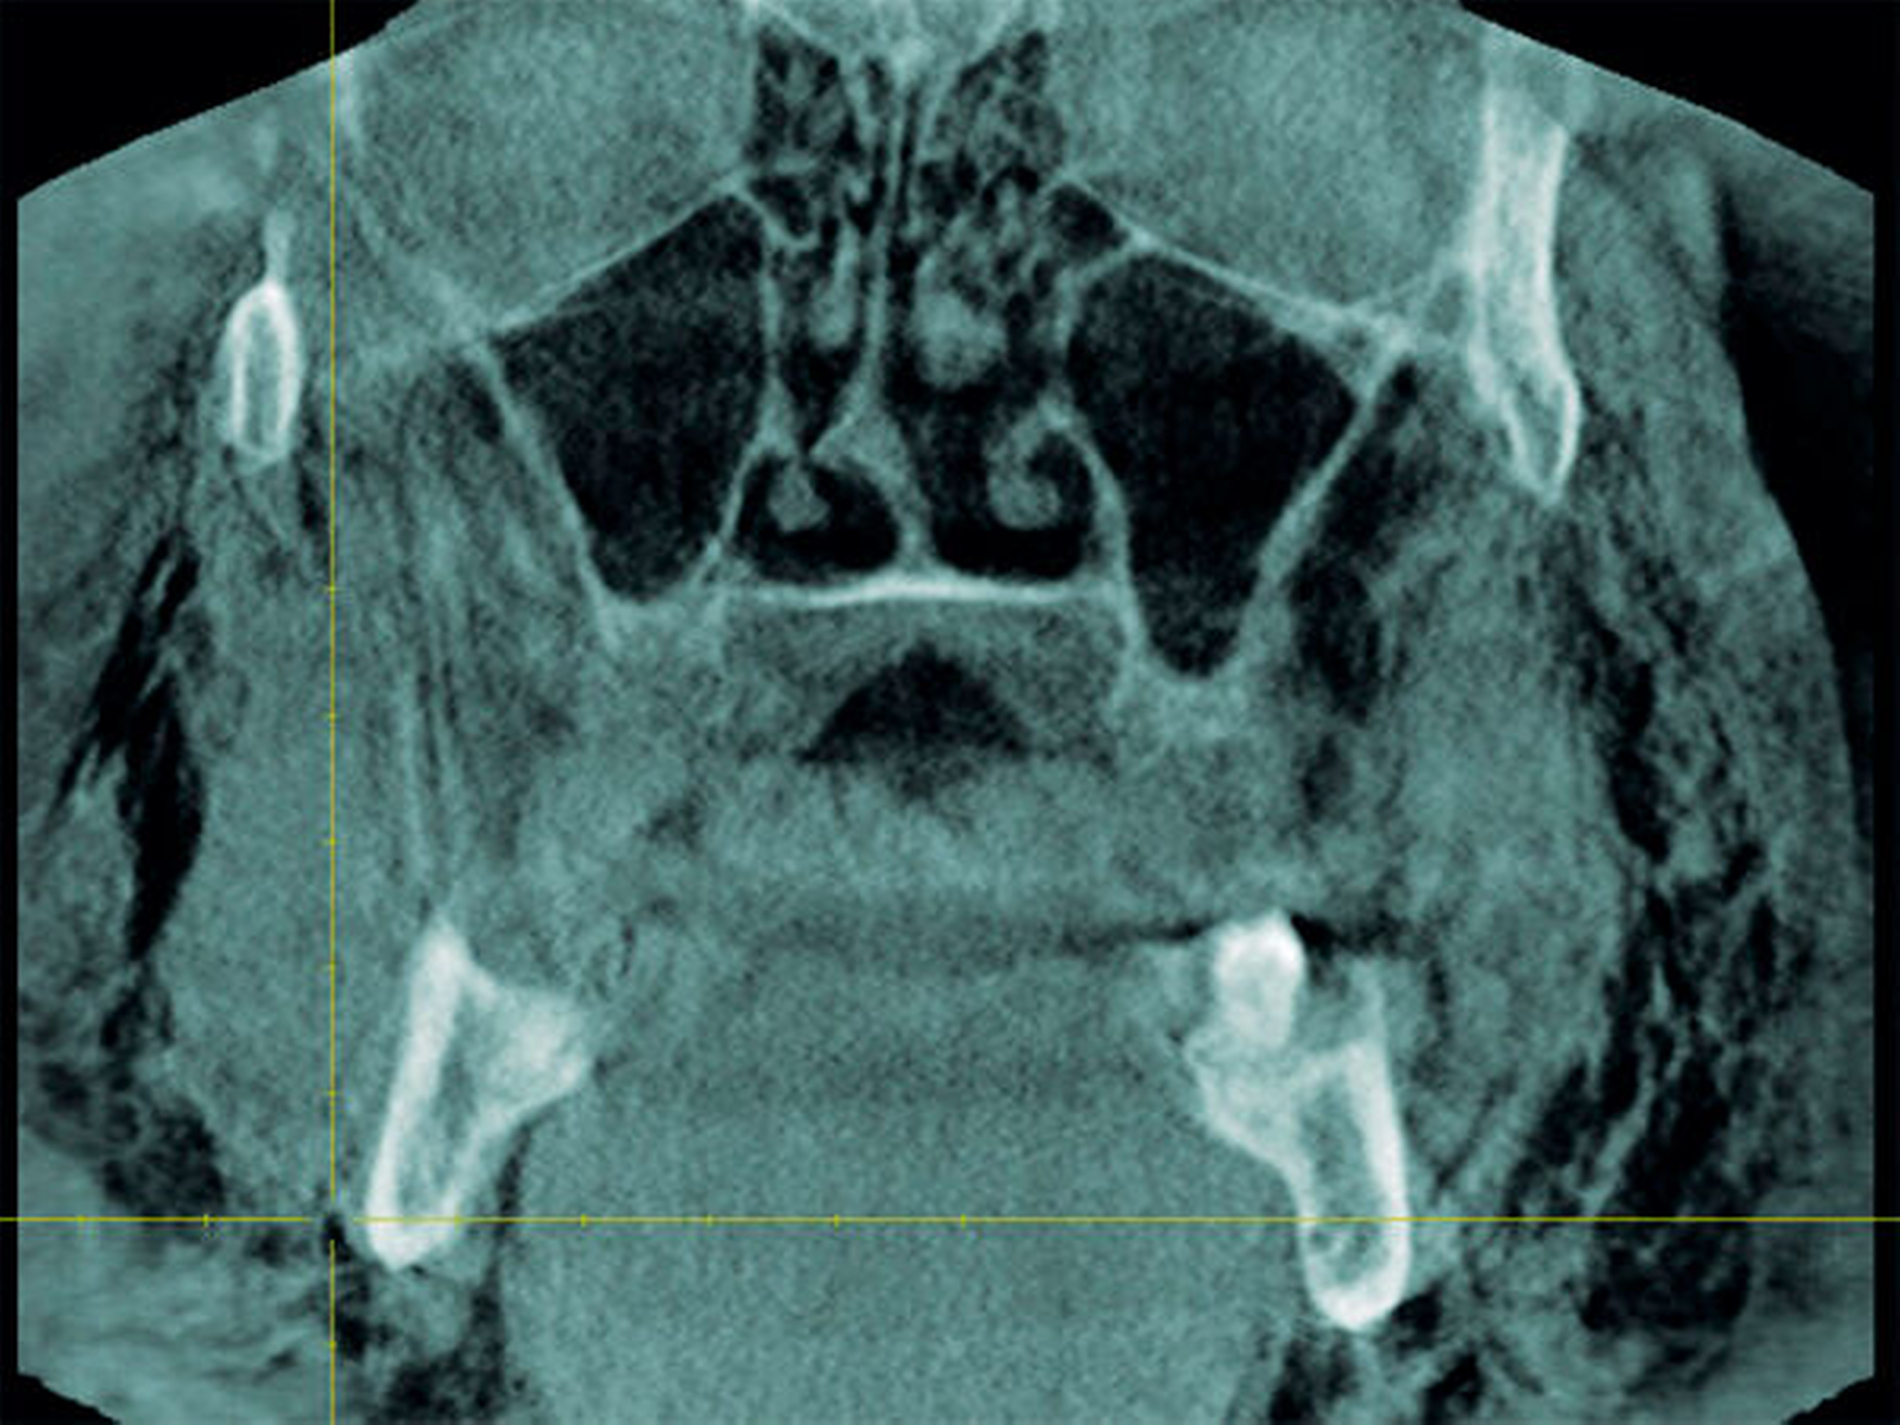

Zum Ausschluss einer Mittelgesichtsfraktur bei palpatorischem Weichteilemphysem erfolgte zur weiteren Diagnostik eine DVT-Aufnahme. Es zeigten sich keine Frakturen im Bereich des Mittelgesichts oder der Kiefer. Jedoch kam in der DVT-Bildgebung sowie in der OPT-Optik ein massives Weichgewebeemphysem zur Darstellung (Abbildungen 2 bis 5).

Weiterhin wird deutlich, dass bei in aller Regel doch sehr eingeschränkter Beurteilbarkeit von Weichgewebe im DVT in diesem speziellen Fall eine weiterführende Diagnostik und Therapie eingeleitet werden konnte.

Das Emphysem war initial im DVT so eindrucksvoll sichtbar, dass es trotz fehlender klinischer Symptomatik im Thoraxbereich, schwieriger Anamnese und blander zweidimensionaler Bildgebung der Lunge (RÖ-Thorax) der Faktor für eine weitere dreidimensionale Bildgebung (CT-Thorax) war, die letztendlich die Verdachtsdiagnose sicherte.

Zur Frakturdiagnostik im Mittelgesichtsbereich eignet sich das DVT sehr gut, außerdem ist die freie Luft des Emphysems im undifferenzierten Weichgewebe gut darstellbar.

Mittels der digitalen Volumentomografie können Weichteile schlecht bis gar nicht beurteilt werden, Lufteinschlüsse im Weichgewebe hingegen können gut dargestellt werden.